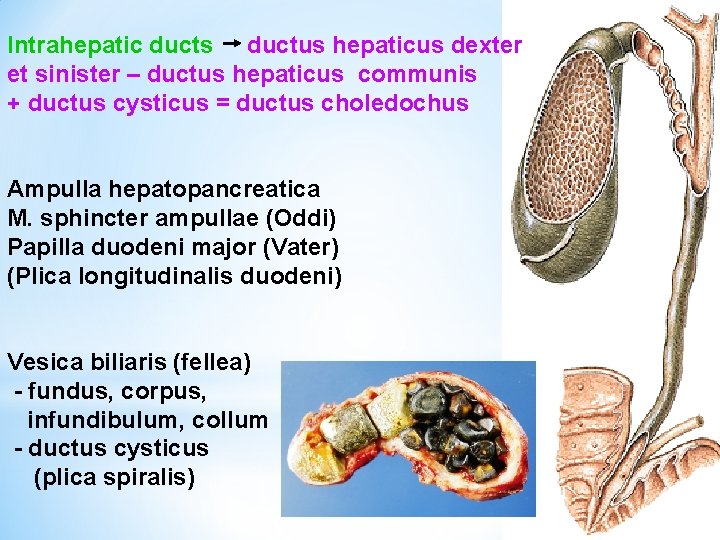

Intrahepatic ducts ductus hepaticus dexter et sinister – ductus hepaticus communis + ductus cysticus = ductus choledochus Ampulla hepatopancreatica M. sphincter ampullae (Oddi) Papilla duodeni major (Vater) (Plica longitudinalis duodeni) Vesica biliaris (fellea) - fundus, corpus, infundibulum, collum - ductus cysticus (plica spiralis)